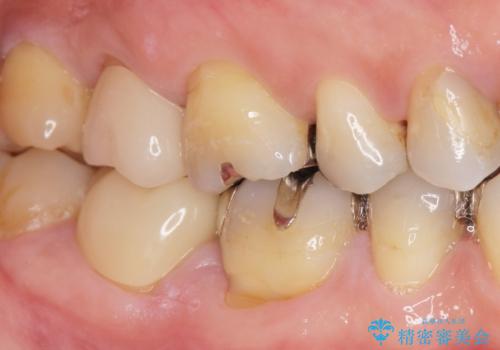

移植がうまくいかない可能性を考慮し、ブリッジもできるよう隣の親知らず(右上8)は残し、反対側の親知らず(左上8)を移植しました。

「状態の悪い銀歯がなくなりすっきりした」と喜んで下さいました。

見た目や使用感にご満足頂き、他の部位も現在治療中です。

クラウンの種類:オールセラミッククラウン ベレッツァ